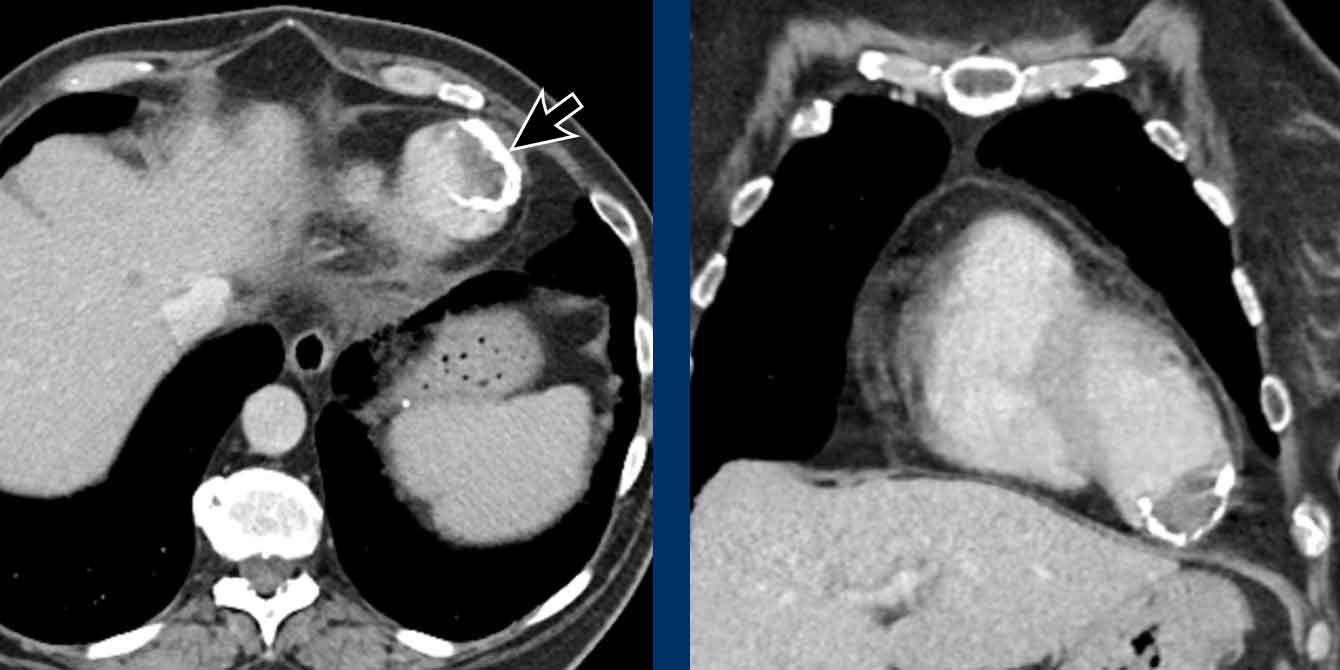

Hình ảnh

Bệnh nhân này được lên kế hoạch cắt thùy trên phải do ung thư phổi và bất thường mạch máu này ban đầu đã bị bỏ sót trên hình ảnh CT.

Những hệ quả trong phẫu thuật của bất thường như vậy nhấn mạnh tầm quan trọng của việc không bỏ sót các biến thể này.

PAPVR bên trái phát hiện tình cờ với dẫn lưu trên tim của máu từ thùy trên trái vào tĩnh mạch tay đầu trái (các mũi tên).